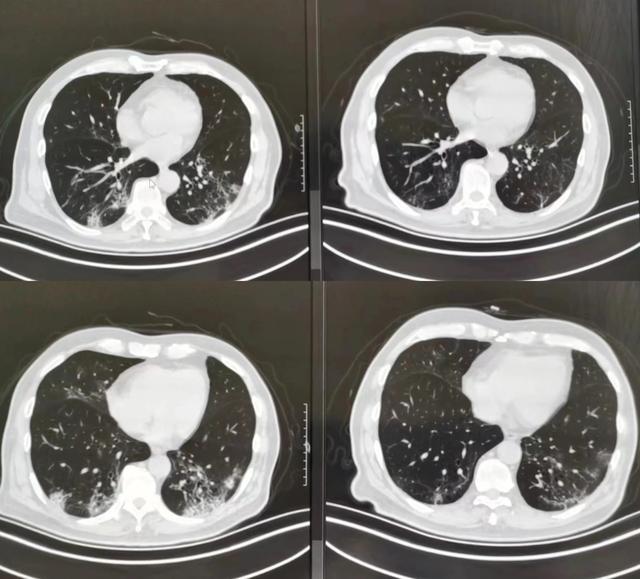

一例肺间质性纤维化

图片尺寸1602x1128